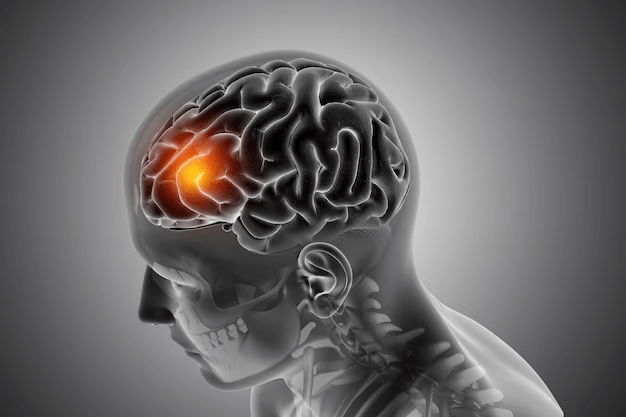

As lesões cerebrais são danos físicos ao encéfalo, que podem ocorrer devido a traumas, Acidentes Vasculares Cerebrais ou doenças neurodegenerativas, como Parkinson e Alzheimer. Elas podem afetar diversas funções cerebrais, como a cognição, a memória, a linguagem e movimento

Dependendo da gravidade da lesão e da área afetada, o paciente pode ter sequelas irreversíveis que, mesmo com a neuroplasticidade, a habilidade do cérebro de se adaptar a mudanças e lesões, ainda causam danos crônicos ao paciente.